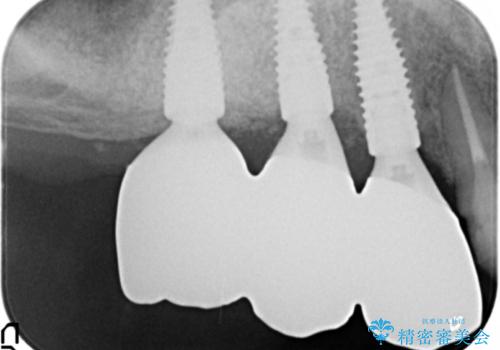

精査したところ、歯周病に罹患した歯を長年放置したことから骨吸収が進行し、上顎骨の厚みはとても薄くなっていました。

全顎的な歯周病治療を行ったのち、上顎洞底挙上術(上顎骨に骨を増やす手術)を併用したインプラント埋入を行いました。

- ¥1,400,000 (上顎洞底挙上術、GBR、インプラント×3本、アバットメント×3本、仮歯×3本、被せ物×3本)費用は治療当時の料金となります

インプラントの種類:ストローマン BLT